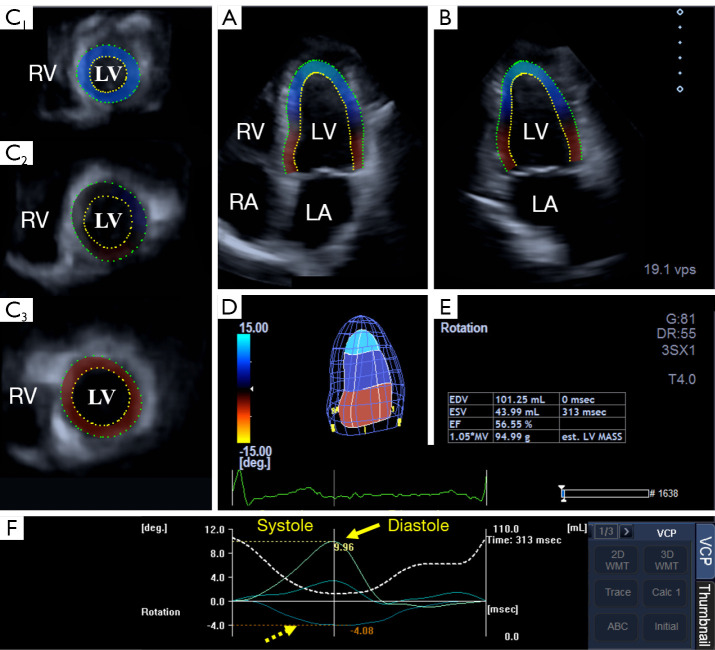

Background: The Fontan procedure (FP) is a surgical palliation diverting blood flow from the caval veins to the pulmonary artery. The FP is used in several congenital heart diseases (CHDs), for instance in the absence of a heart valve and/or in the presence of an abnormality of a heart chamber. Since little information is available on the cardiac mechanics of FP-operated patients, the present study aimed to determine three-dimensional speckle tracking echocardiography (3DSTE)-derived basal and apical left ventricular (LV) rotations in adult patients with CHD mainly affecting the right heart late after FP.

Methods: The present study comprised 15 CHD patients late after FP with a mean age of 32.6±8.0 years (5 males). Their results were compared to a group of 25 age- and gender-matched healthy individuals (mean age: 33.4±11.9 years, 8 males).

Results: Regarding the type of the procedure, bidirectional Glenn procedure (BDGP), modified Kreutzer procedure (MKP) and total cavopulmonary connection were performed as final palliative procedures in 2, 3 and 8 patients, respectively. Regarding the ventricular anatomy, hypoplastic right heart syndrome (HRHS), univentricular heart (UH) and tricuspid atresia were present in 3, 5 and 5 patients, respectively. With 3DSTE, regarding the procedure, only MKP patients showed normal LV ejection fraction (EF) due to increased LV end-diastolic volume (EDV), other groups showed mildly reduced LV-EF. With 3DSTE, regarding the ventricular anatomy, UH patients had the largest LV-EDV, but no differences could be detected in mildly reduced LV-EF values between the subgroups. Regarding the procedure, BDGP patients had larger basal and apical LV rotations compared to the other groups resulting in increased LV twist. Regarding the ventricular anatomy, HRHS patients had larger basal and apical LV rotations compared to the other groups resulting in increased LV twist.

Conclusions: In FP patients with CHD mainly affecting the right heart, on a group level, impaired LV-EF is associated with tendentiously lower LV twist due to reduced apical LV rotation, but characteristics of LV functional and rotational mechanics show substantial differences depending on the ventricular anatomy in CHD and the procedure performed.